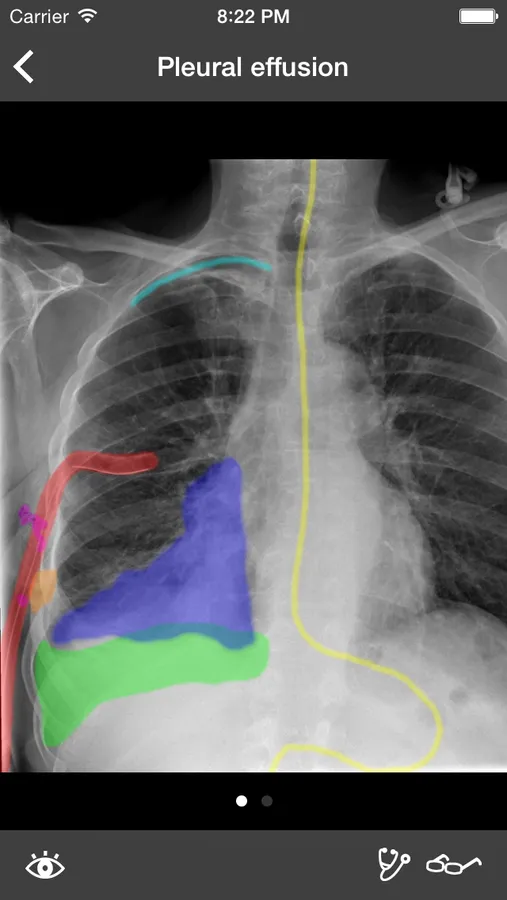

RealWorld Radiology is your ultimate guide to the basics of thoracic imaging. Learn to read chest X-rays in no time and discover the most frequent diagnoses through multiple fully annotated examples.

- High-resolution X-rays

- Drawings of every radiological finding right on the X-ray

Our cases have been especially selected for their high pedagogical value and real-world representativeness. They can be classified either by diagnosis (e.g. pneumonia, atelectasis, pulmonary fibrosis) or by actual radiological finding (e.g. alveolar opacities, interstitial opacities, silhouette sign), making the learning of the differential diagnosis easier than ever while keeping each case easy to find for quick access.